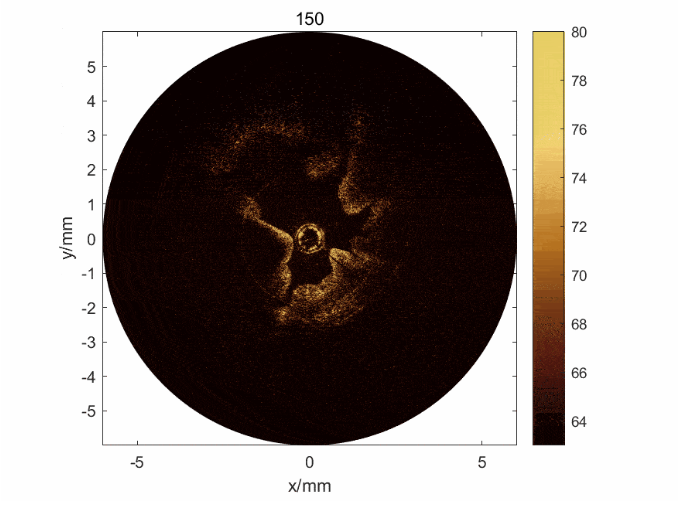

針對這一臨床問題,研究團隊開發了一種基于OCT/超聲的雙模態內窺成像系統。該系統可以獲取整個子宮內膜、從表面到深層的三維信息,其中OCT可以實現內膜的精細成像,超聲可以實現內膜的整體成像;并且基于該系統,實現了對子宮內膜損傷的量化評估分析。

在子宮內膜損傷模型兔中,該雙模態內窺系統實現了世 界上首 個小動物活體內窺成像,并區分了健康和受傷的子宮內膜組織。而量化評估分析的結果進一步證明,結合兩種模態,相對單個模態,明顯提升了對內膜損傷評估的準確性。本工作論證了該技術用于評估子宮內膜容受性的價值,并展現出應用于生殖健康以及診斷子宮其他疾病的臨床潛力。

圖2: a) 子宮內膜損傷模型兔的OCT/超聲圖像及其圖像分割和量化方法; b) 通過雙模態獲取的信息可以判斷子宮內膜的損傷程度,驗證了雙模態的必要性